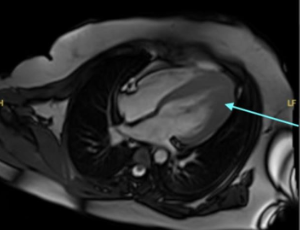

Intermittent Pre-Syncope after Surgical Correction of Aortic Stenosis Caused by Left Ventricular Outflow Obstruction by Elongated Mitral Leaflets

Left ventricular outflow obstruction (LVOTO) is a potential complication following surgical replacement of the aortic valve. We present an 88-year-old man who experienced periodic episodes of pre-syncope following aortic valve replacement. The underlying cause was identified as LVOTO resulting from elongated mitral valve leaflets. The diagnosis was established using stress echocardiography, which detected transient LVOTO with moderate rise in heart rate.